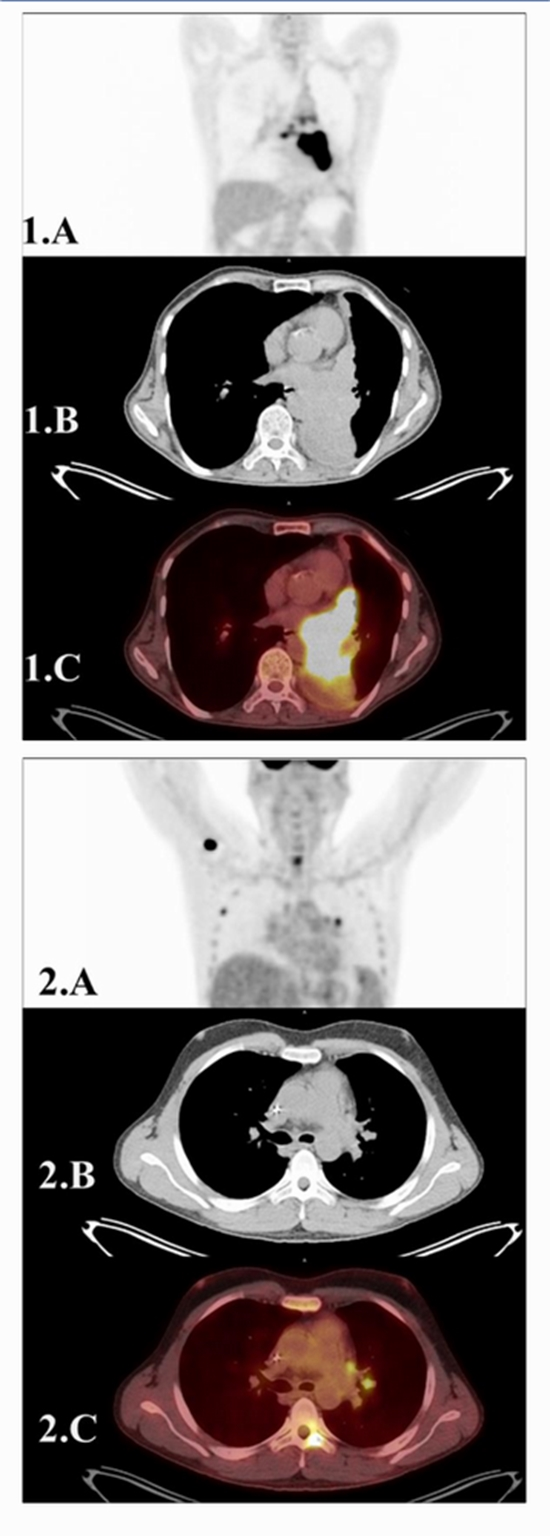

The Role of 1H/MRS and [ 18F]FDG PET/CT in differentiating primary squamous cell carcinoma and metastatic Hodgkin’s lymphoma in lung: An experimental pilot study

Introduction: Distinguishing the cellular origin of lung cancer is essential for tailored patient care. This pioneering pilot study explores the synergy of 1H-Magnetic Resonance Spectroscopy (1H-MRS) and 2-[18F] fluoro-2-deoxy-D-glucose positron emission tomography/computed tomography ([18F]FDG PET/CT) in the differentiation of primary squamous cell carcinoma (SCC) of the lung from Hodgkin's lymphoma (HL) metastases.

Methods: Ethically approved, the study enrolled 21 participants with confirmed lung lesions (10 SCC, 11 HL). [18F]FDG PET/CT and 1H-MRS were conducted, and analyses were performed to assess diagnostic potential.

Results: Significant differences in [18F]FDG PET/CT parameters (SUV max BSA, SUV max LBM, and ID%) between SCC and HL were observed. Metabolite concentrations (Cho, Lac, Cr) from 1H-MRS also exhibited distinctions. Correlations between PET values and metabolite concentrations hinted at links between glucose metabolism and molecular composition. Conclusion: This study presents an innovative approach, integrating 1H-MRS and [18F]FDG PET/CT to distinguish primary from metastatic lung lesions. The results hold promise for improving non-invasive diagnostic accuracy and guiding targeted therapies. Future research should validate these findings and explore the potential for clinical integration.